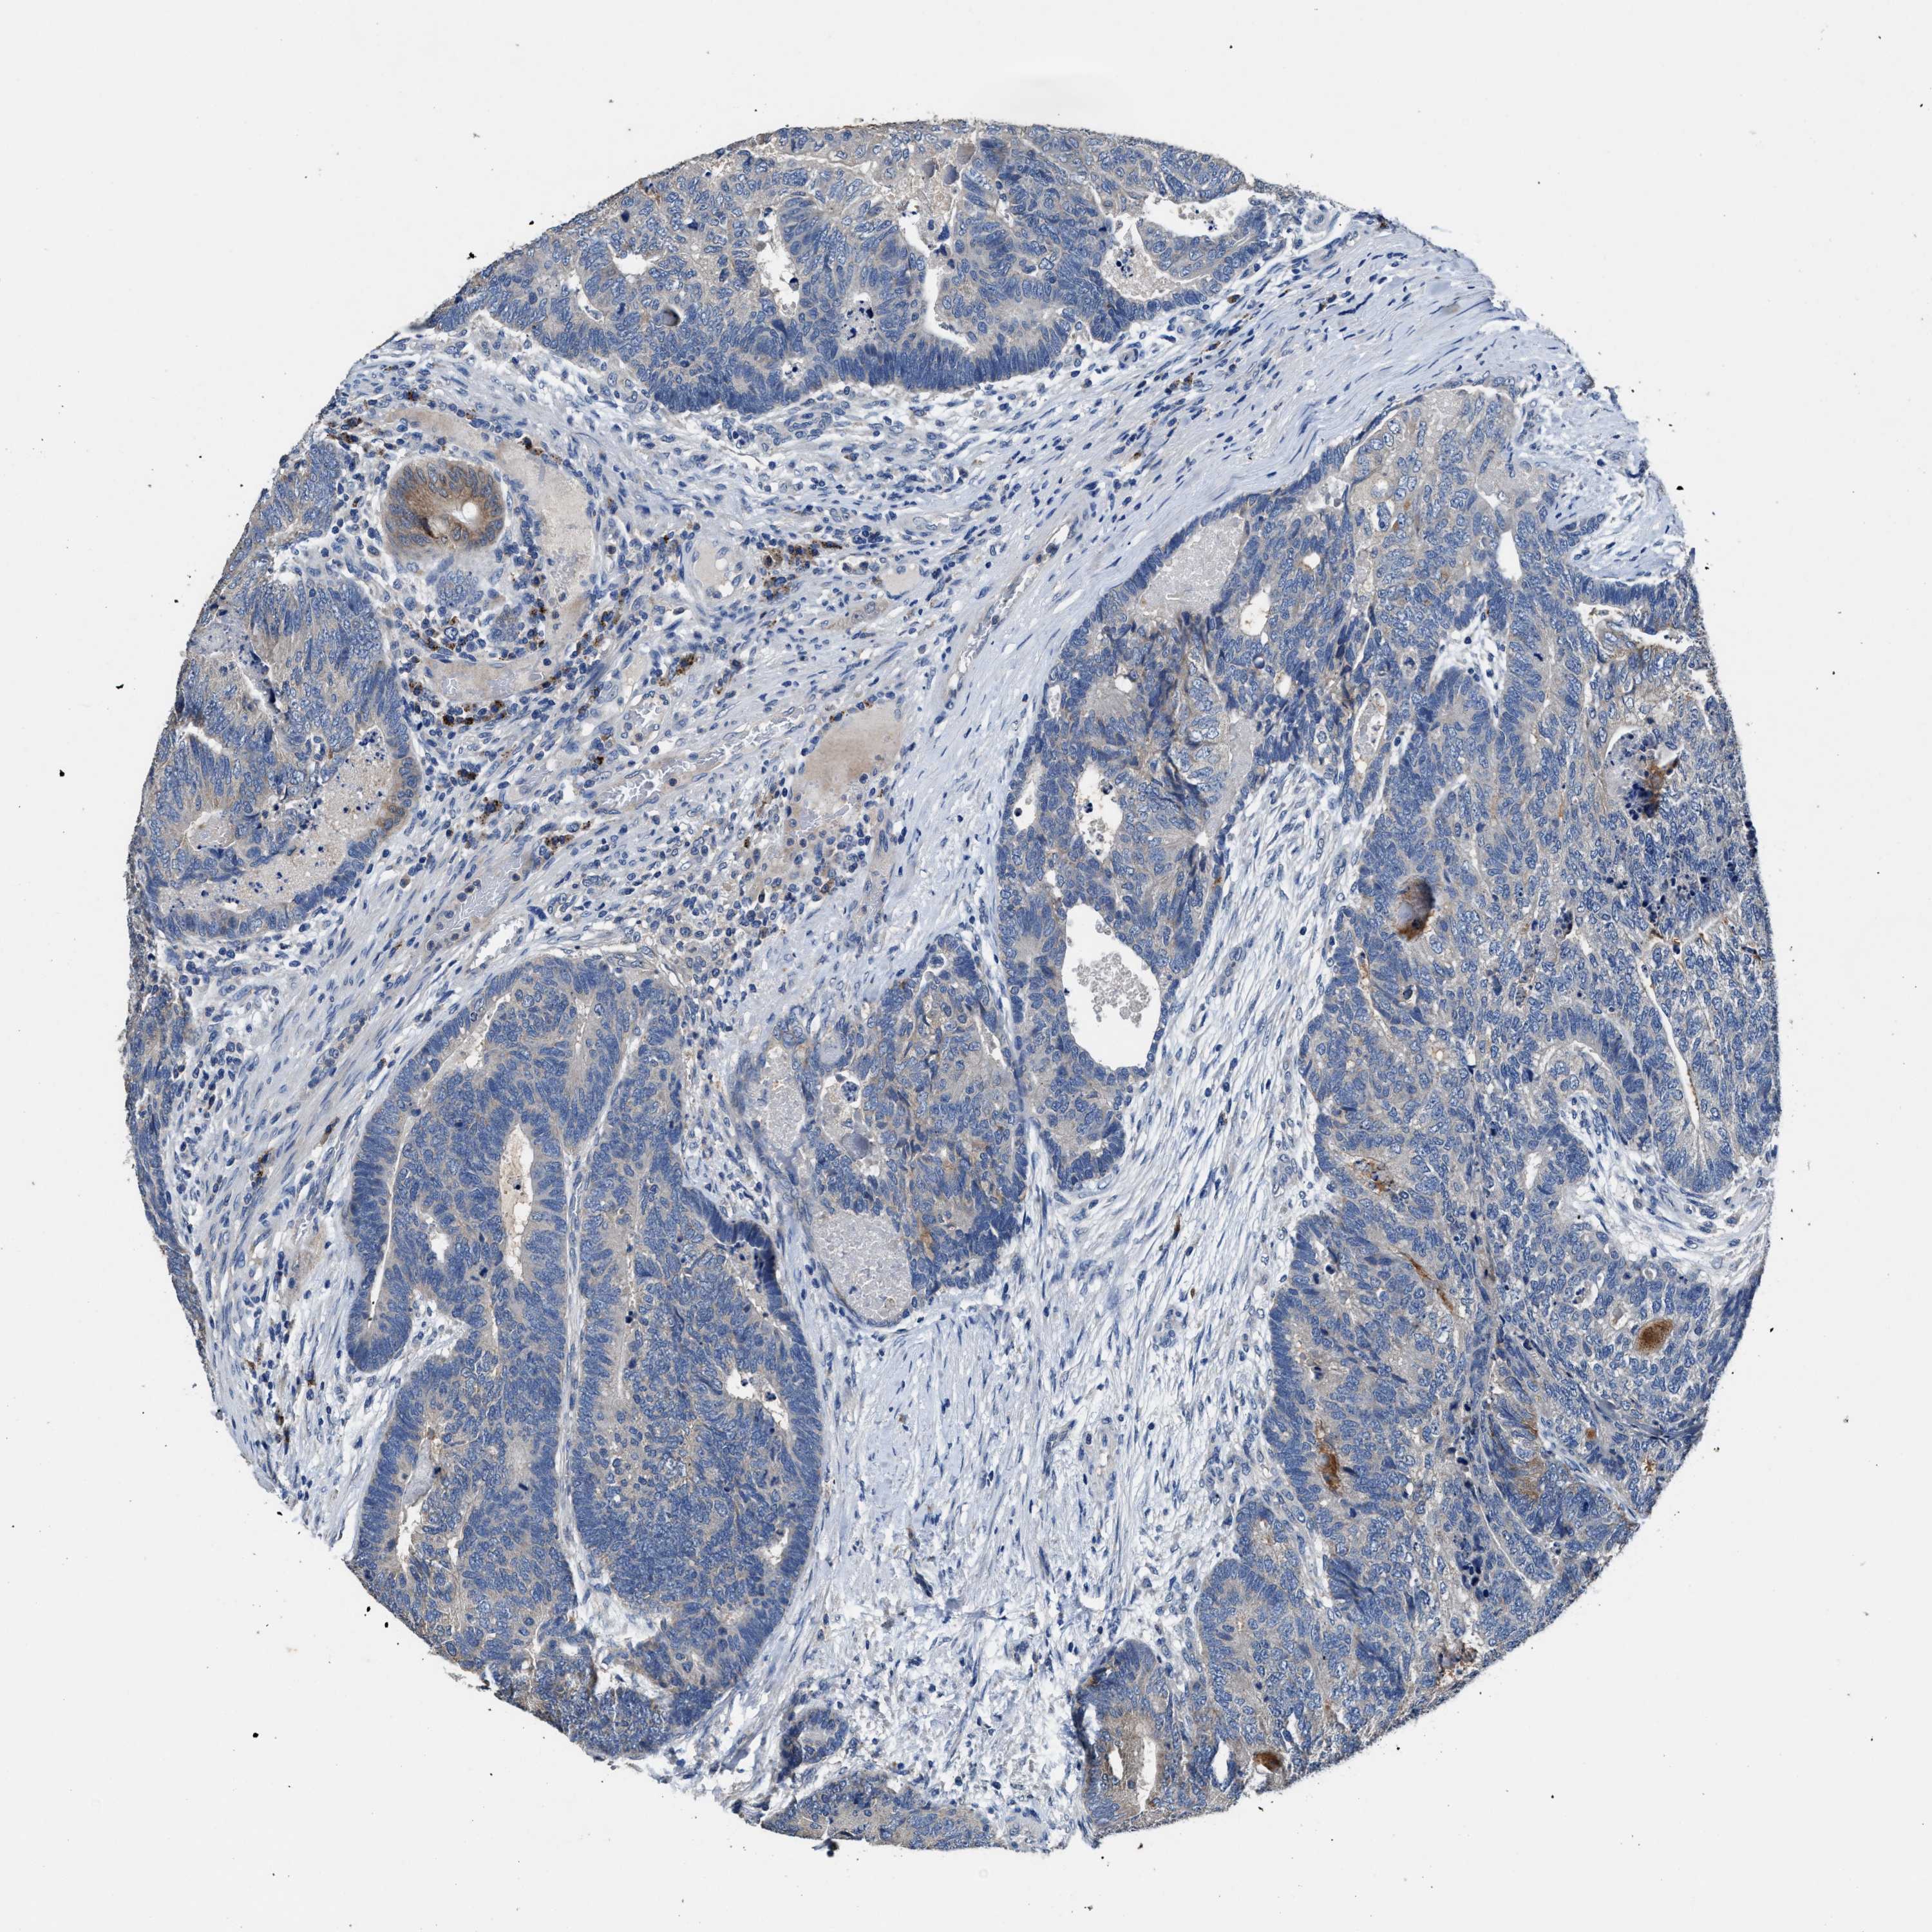

CANCER COLORECTAL CANCER Show tissue menu

ANTIBODIES

AND

VALIDATION